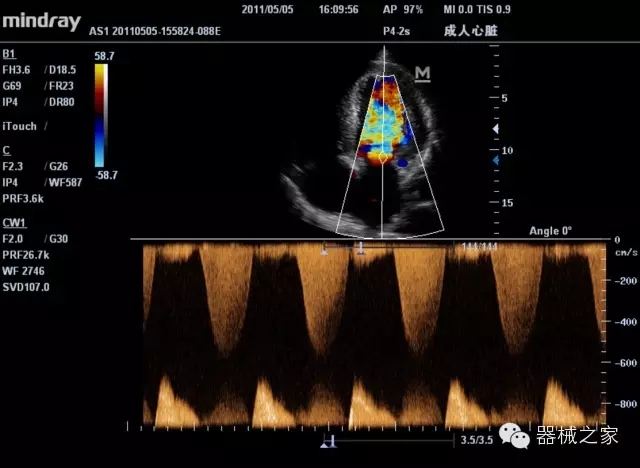

臨床圖片賞析